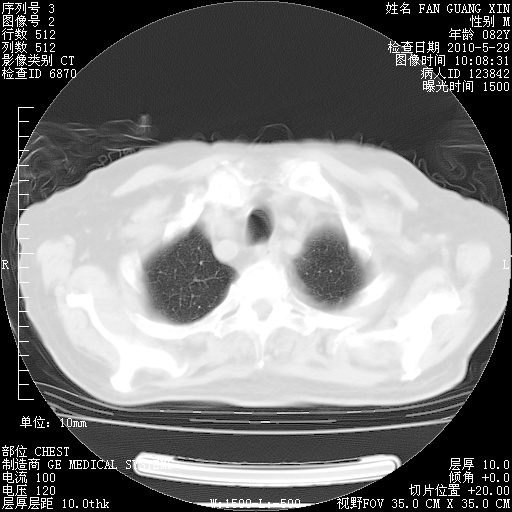

再治疗10天后的肺部CT

阅读此次胸部CT,肺间质渗出性改变较入院时有吸收。目前从体温、白细胞、中性分叶明显增高,肯定存在细菌感染(发生医院感染哦,若无消化道及泌尿系统等感染的依据,肺部感染可能大)。若你院头孢哌酮舒巴坦钠耐药率较高,同意你的方案,若48小时体温仍高,可考虑使用碳青霉稀类抗菌药物,同时可予超声雾化、注意滴数时加大液体量。白蛋白33.30g/L较低哦,需加强营养等支持治疗。